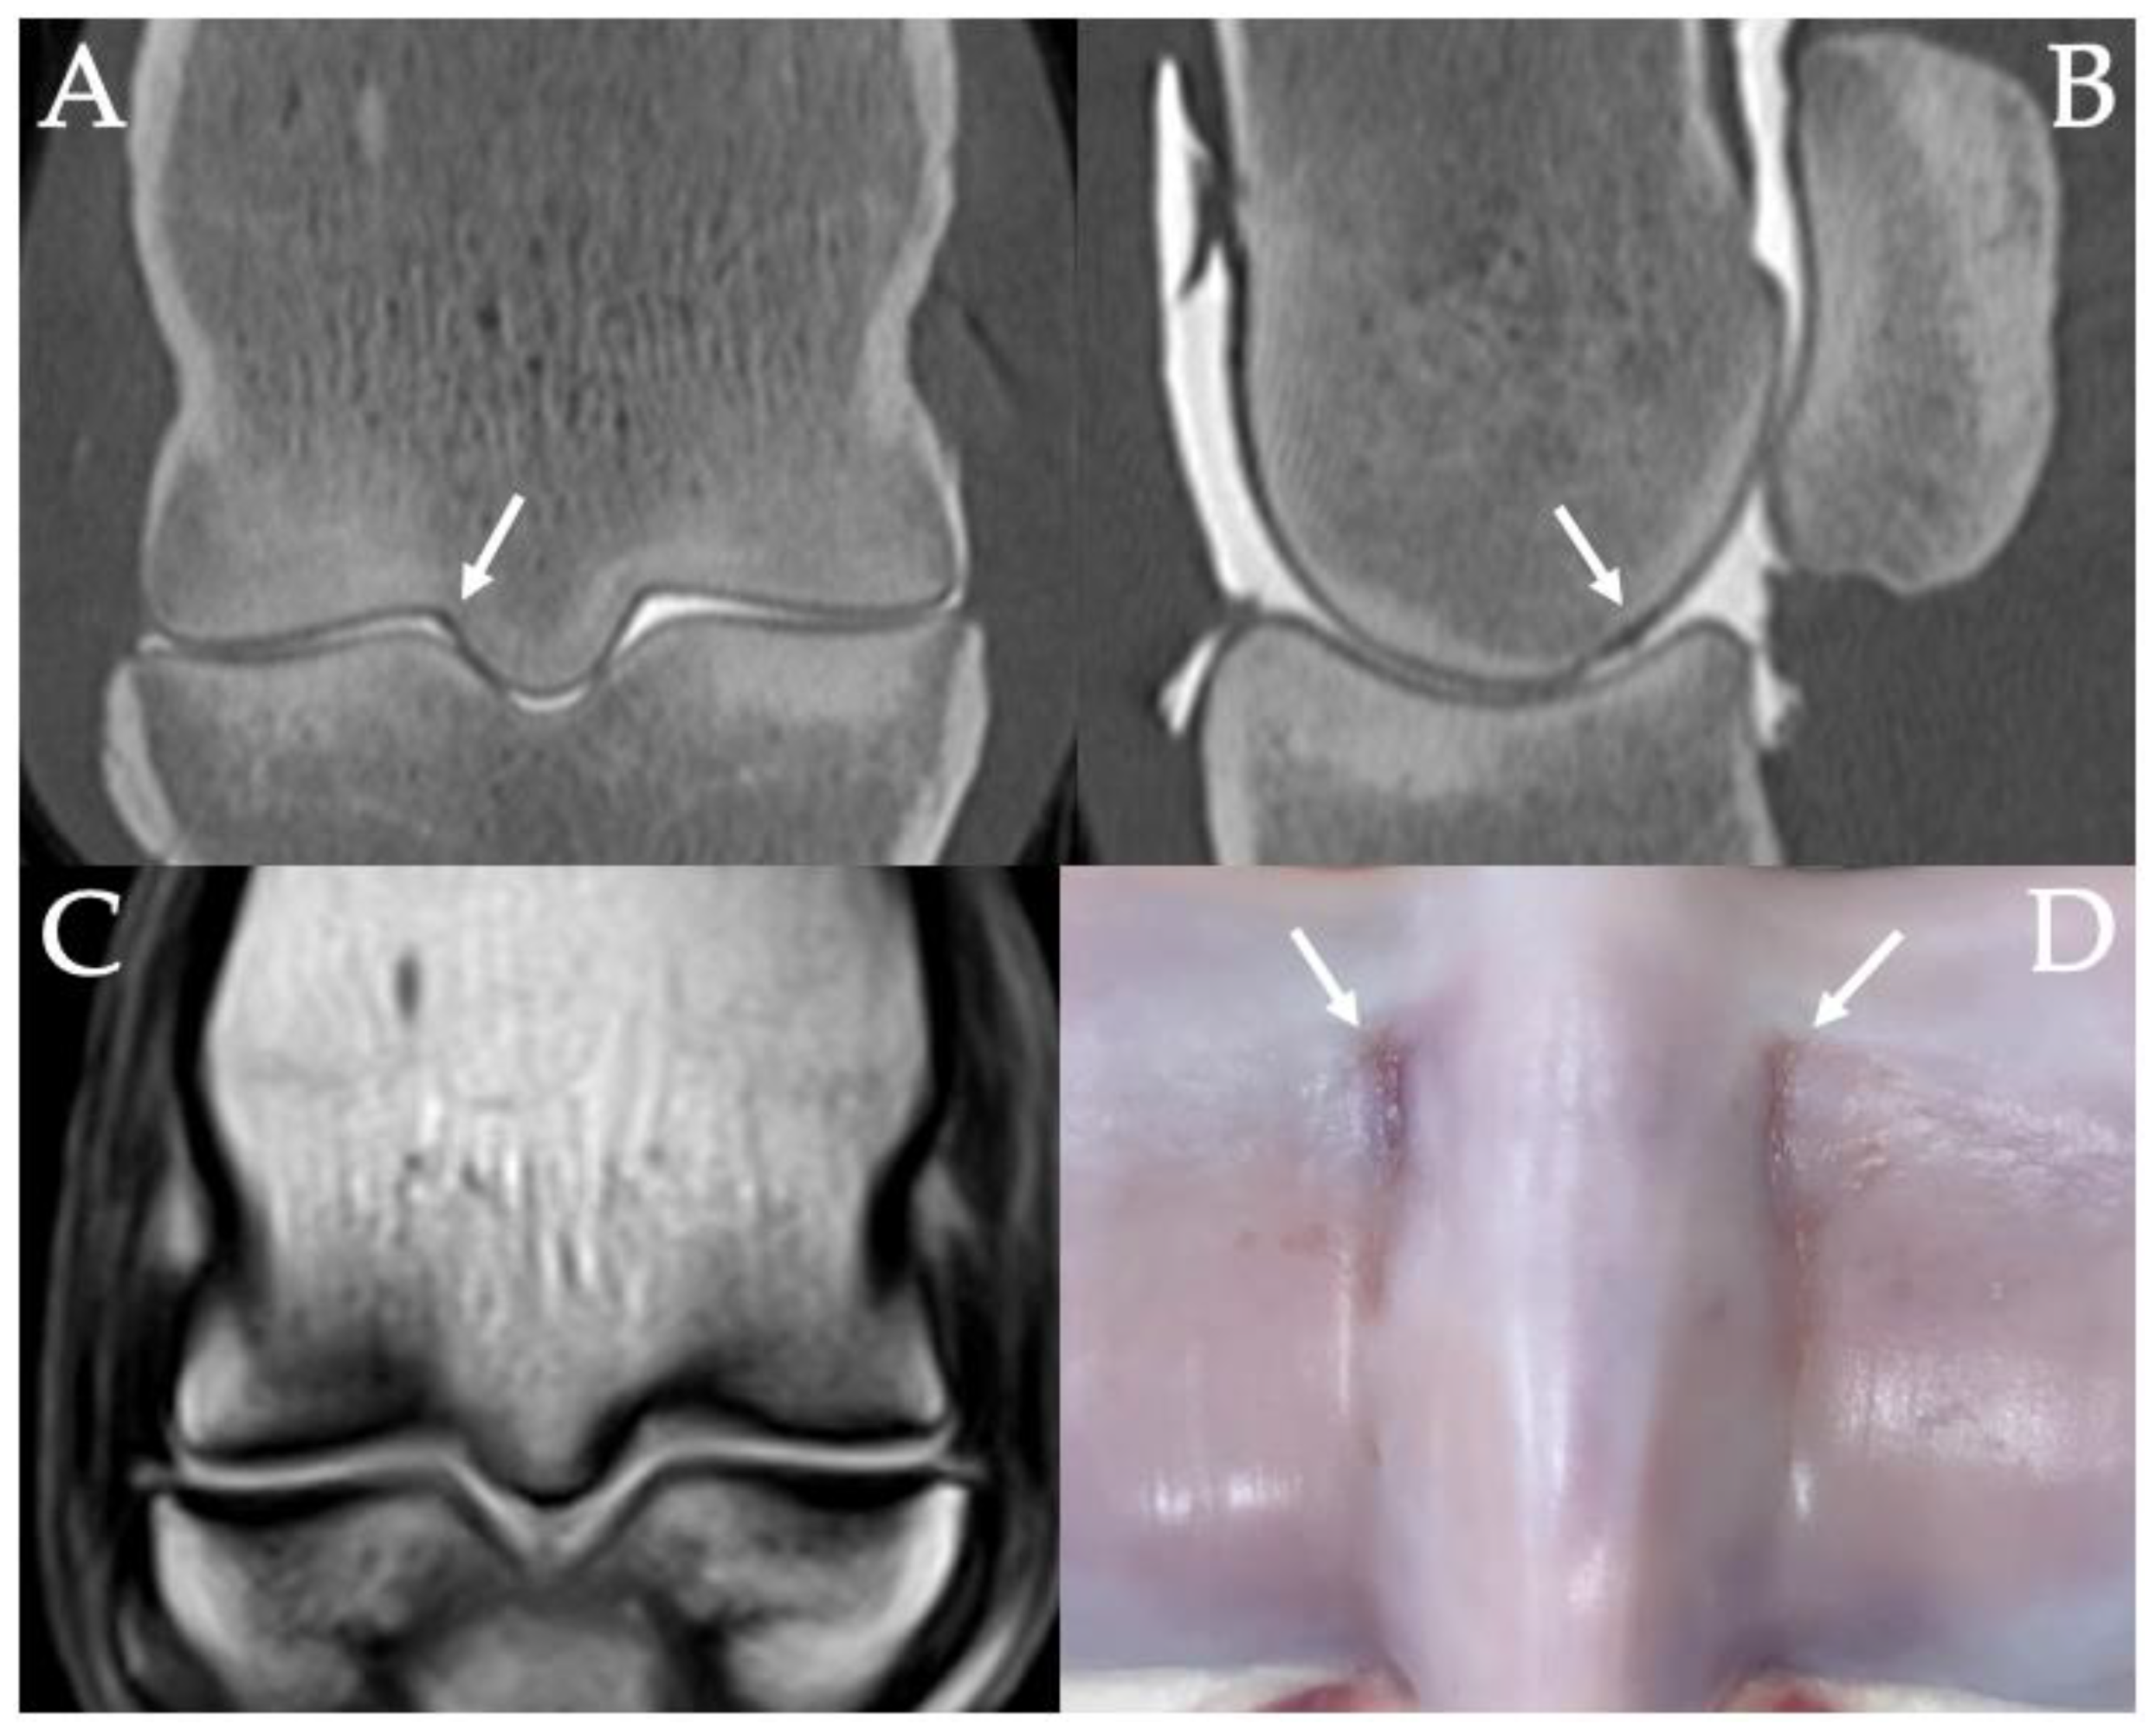

3.2. Sclerosis of the Subchondral and Adjacent Medullary Bone of the PSGs

3.3. PSG Subchondral Bone Lysis

3.4. PSG Subchondral Bone Defects

3.5. PSG Cartilage Defects